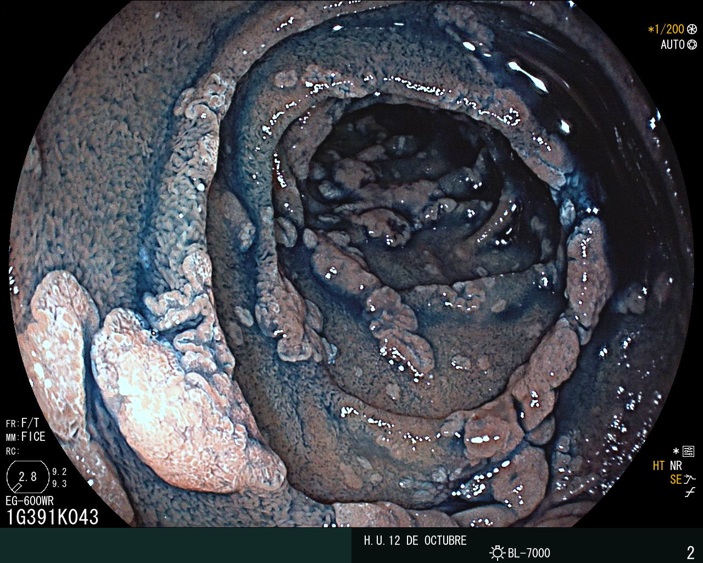

Duodenal adenomas (picture) are a common problem in the upper GI of the patients with familial adenomatous polyposis (FAP)

ESD for these big lesions is indeed a useful endoscopic technique after optical diagnosis with magnification is done.

In LGD, regular V and S patterns are present. Regular WOS may also be seen as was the case with this patient with a pathogenic mutation in APC

After a successful en bloc resection, the final specimen (37×37mm, tumor size 21×21mm) was retrieved. LGD was confirmed for this 0-IIa+IIc lesion (as observed in previous biopsies)

But another small lesion was also observed during the procedure

Chromoendoscopy and magnification were done

After watching this latter video, what is your diagnosis?